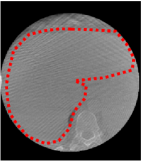

An example of CT/CBCT and MR/CBCT registration results are shown in figures 3 and 4, respectively. For both cases, the CBCT image (first column) was acquired intra-operatively after needle insertions and was employed as a reference for image registration. The pre-operative image is displayed before registration (second column), after PM-EA (third column) and after PM-EA+Evo (fourth column). The occurrence of patch shifts is reported for each spatial direction in panels (m–o): for each histogram, the shift with maximal occurrence is shown by the red dashed line. For panels (a–l), a ROI — manually defined on the CBCT image/encompassing the liver — is shown using red dash lines. Our visualization shows an improved correspondence of the contour of the liver with the manually defined liver boundary when the PM-EA solution is employed (see 3(c,g,k) and 4(c,g,k)). Moreover, an even better correspondence of the contour is observable using the PM-EA+Evo solution (see 3(d,h,l) and 4(d,h,l)).

Trans.

[X-Y]

CBCT

(a)

CT / No registration

(b)

CT / PM-EA

(c)

CT / PM-EA+Evo

(d)

Sag.

[X-Z]

(e)

(f)

(g)

(h)

Cor.

[Y-Z]

(i)

(j)

(k)

(l)

(m)

(n)

(o)